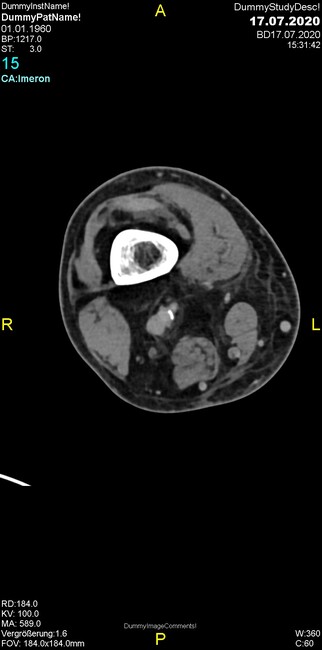

Um welche Modalitäten handelt es sich?

- Röntgen p.a. und lateral, CT coronar Knochenfenster, CT axial Weichgewebsfenster

- Röntgen p.a. und lateral, CT coronar Weichgewebsfenster, MR axial

Was fällt in der Projektionsradiographie auf?

- Verdichtung im Recessus suprapatellaris

- Aufhellungslinie in Projektion auf die Femurkondylen

- Erhöhter tibialer Slope

- Hypertransparenz tibial

- Subluxationsstellung im Kniegelenk

Was trifft auf den Befund zu?

- Der Befund beschränkt sich auf den Knochen.

- Es besteht hochakuter Handlungsbedarf.

- Der Befund ist tendenziell benigne.

- Der Befund ist tendenziell maligne.

- Der Befund weist einen Zusammenhang zum Patientenalter auf.

Was fällt in der CT im Knochenfenster auf?

- Mediale Gelenkspaltverschmälerung

- Dezente Erosion der fibulären Kortikalis

- Frakturspalt der lateralen Tibiametaphyse

- Weichgewebskalzifikationen lateral angrenzend an den Gelenkspalt

- Osteolyse der Tibiametaphyse unter Beteiligung der Kortikalis

Was kommt differentialdiagnostisch in Frage?

- Kompartmentsyndrom

- Osteomyelitis mit Weichgewebsanteil

- Metastase mit pathologischer Fraktur

- Rheumatoide Athritis

- Posttraumatische Verletzung